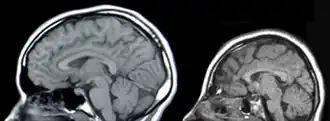

Microcefalie is een afwijking van het centrale zenuwstelsel waarbij de schedelomvang te klein is. Het is meestal een aangeboren aandoening. De hersenen ontwikkelen zich niet goed waardoor de schedel ook kleiner blijft. Vaak is er sprake van een verstandelijke beperking.

Er bestaat een primaire en secundaire microcefalie. De primaire microcefalie is vaak autosomaal recessief overerfbaar. Bij een secundaire microcefalie, is er sprake van een secundaire oorzaak.

Microcefalie ontstaat door een chromosoomafwijking, een ontwikkelingsstoornis of een infectie tijdens de zwangerschap. Vaak is het een kenmerk van een syndroom.